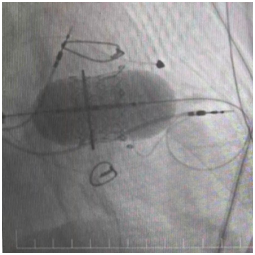

经过心脏外科、心内科、麻醉科、超声科等多学科反复论证,团队最终决定:采用经导管介入技术,一次性完成三大操作——球囊扩张狭窄的三尖瓣、植入新的生物瓣、同时安置永久起搏器。

三尖瓣置换术

“这相当于用微创的方式,完成过去需要三次手术才能解决的问题。”陈文生主任解释说,介入操作无需再次开胸,只需通过血管穿刺送入导管,对患者创伤小,尤其适合这种多次手术后的高危患者。

手术台上,心脏大血管外科陈文生团队通过细致的影像引导,将球囊送至原有瓣膜处进行扩张,随后将新的生物瓣精准释放在预定位置。最后,在心脏稳定的状态下,顺利植入了永久起搏器。整个过程中,患者生命体征平稳。